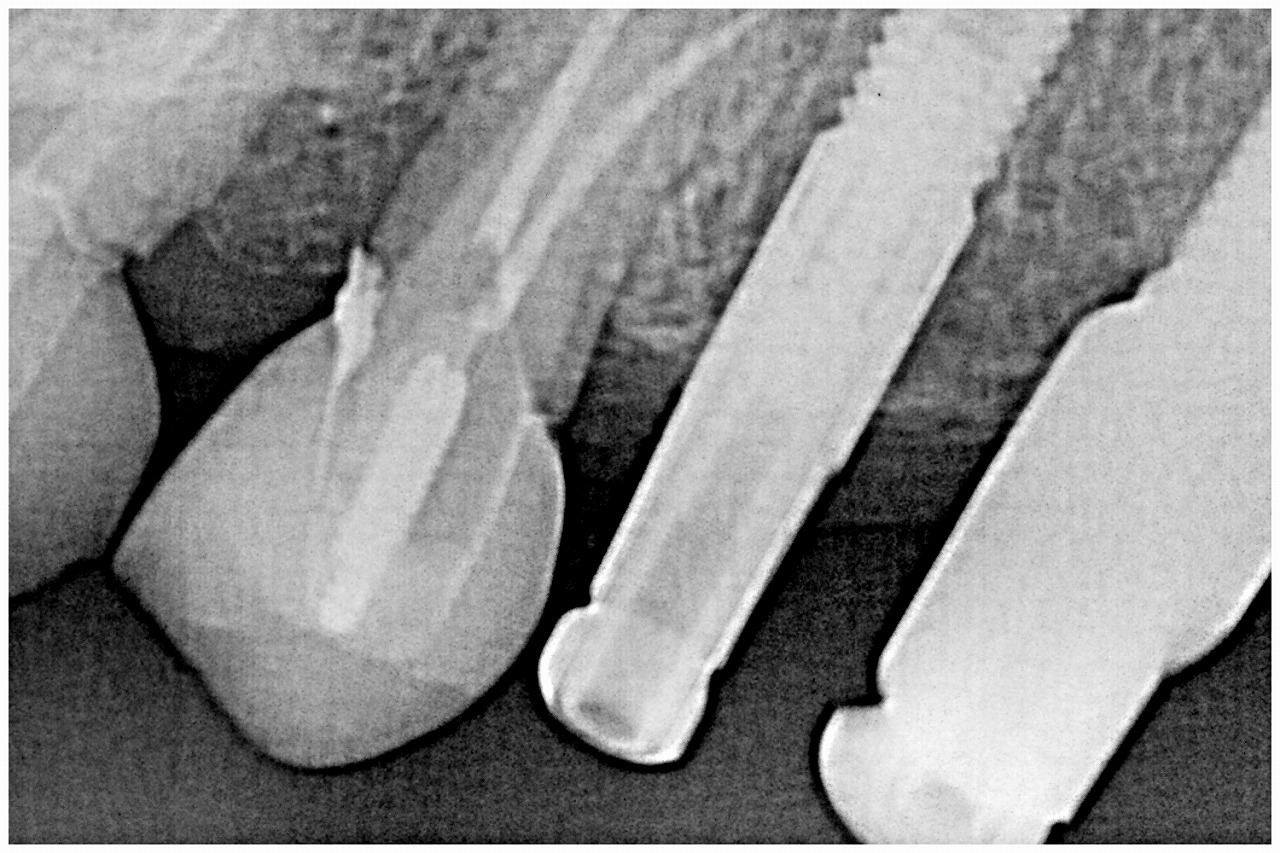

ブログ一覧|広島市安佐南区の歯科医院 ブログ一覧 トップ ブログ一覧 お知らせ スタッフブログ ブログ一覧 お知らせ 2019/09/27 左上7番 被せが割れたので見てほしい 噛むと痛む お知らせ 2019/09/26 治療計画からISIシステムにてわかりやすく説明を行い、多少の変更はありますがほぼけりお角通りに治療を行っています インプラントを使いながらも、長期的に安定の得れる最終ゴールがイメージできることが歯科医師の手腕かと思います お知らせ 2019/09/26 治療期間1年 この当時は院長がほぼこのセラミックをセレックシステムにて作成しました 9年前になりますが、、 お知らせ 2019/09/25 左上3本のインプラントの上部構造が完成しました バイトアップからの上部構造が仕上がりました お知らせ 2019/09/25 左上インプラントの上部構造の作成 セレックシステムにてコピー法にて作成していきます お知らせ 2019/09/24 左上もインプラント埋入を行い、バイトアップしていきます お知らせ 2019/09/21 フルマウスのリコンストラクション 咬合再構成 この咬合の乱れをインプラントも用いて再構成していきます お知らせ 2019/09/21 9月20日より 来る福岡の地の福岡サンパレスにて日本口腔インプラント学会が開催されました 専修医の資格の単位もあり16時からの基調講演を受けに行きました << 1 2 3 4 5 … 382 383 384 385 386 … 870 871 872 873 874 >> Web診療予約 初めての方へ 選ばれ続ける理由 院内設備について 歯が痛いしみる一般歯科 歯がぐらぐらする歯周病 健康な歯を保ちたい予防歯科 子供の虫歯予防をしたい小児歯科 銀歯をセラミックに審美歯科 白い歯を目指しませんか?ホワイトニング 矯正専門医がいるので安心矯正歯科 抜けた歯を補いたいインプラント・入れ歯 医院案内 スタッフ紹介 メリィハウス歯科クリニックオフィシャルホームページ ラベンダー歯科クリニックオフィシャルホームページ お知らせ・ブログ ホーム 診療科目 一般歯科 歯周病治療 予防治療 小児歯科 審美治療 ホワイトニング 矯正歯科 入れ歯・インプラント マウスピース矯正 初めての方へ 院長・スタッフ 設備紹介 医院案内・アクセス メニューを閉じる